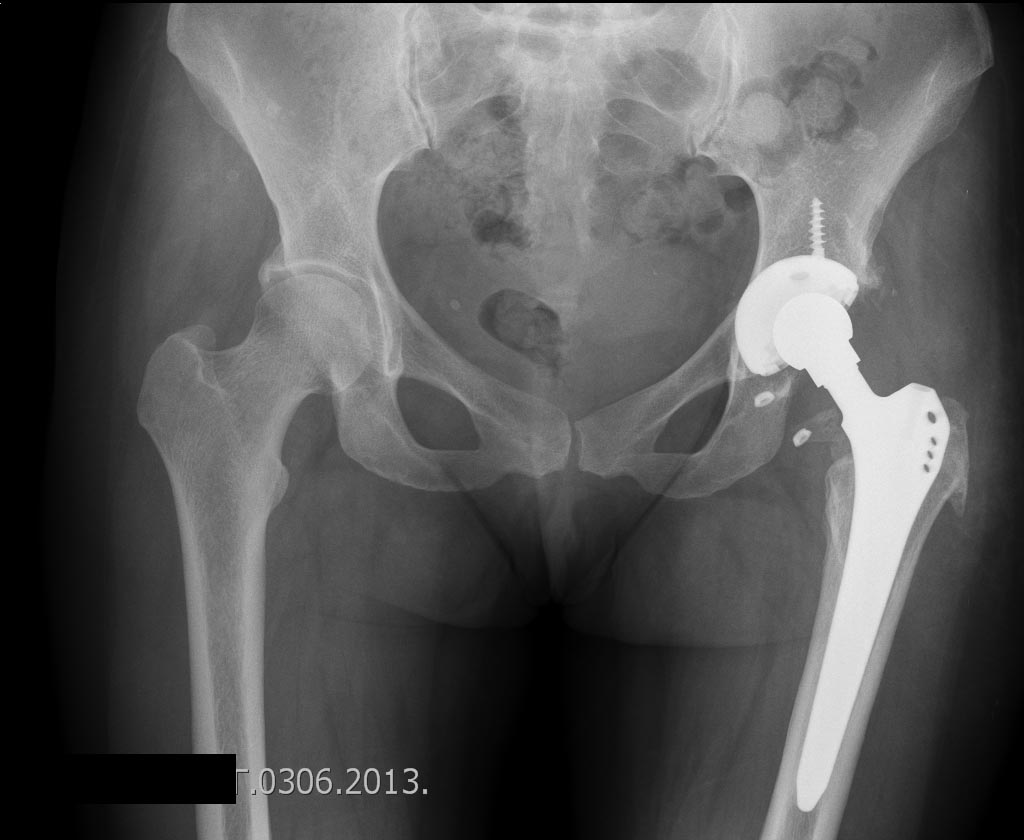

- это и есть нестабильна, сейчас вроде похоже на правду, но нужен таз целиком

Да конечно чашка была нестабильна.Больная завтра идет домой,вот обзорная таза.

Ну вот, другое дело. Сравните снимке до и после, увидете разницу, насколько разнятся стояния чашек и по глубине и по углу инклинации.Молодцы. Я Вас Поздравляю.